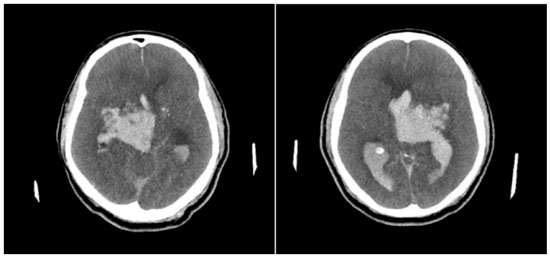

Paciente do sexo masculino, 62 anos, diabético e hipertenso, deu entrada no Departamento de Emergência com queixa de cefaleia súbita e rebaixamento do sensório, 3 horas antes de sua chegada. Seus sinais vitais da entrada mostravam hipertensão com PA 163x110 mmHg, taquicardia com FC 110 bpm, com boa saturação em ar ambiente de 97%, apesar do quadro de rebaixamento e escala de coma de Glasgow de 10 (AO 3 RV 3 RM 4). Poucos minutos após sua chegada, antes mesmo que fosse levado para realizar neuroimagem, paciente apresentou episódio de convulsão tônico-clônica generalizada, ocasião na qual houve piora do rebaixamento. Foi hidantalizado e intubado na sequência. Apesar das medidas para neutroproteção, paciente apresentou instabilidade hemodinâmica, com hipotensão de 92x57 mmHg. Não havendo condições de transporte para realizar neuroimagem, foi realizado ultrassom beira leito da bainha do nervo óptico, que mostrou aumento desta com achado de 8,42 mm de dilatação, corroborando com a hipótese de hipertensão intracraniana que ditava o quadro clínico. Foram iniciadas medidas para aumento da pressão intracraniana, assim como correção da hipotensão, com posterior estabilização hemodinâmica. Realizou, então, neuroimagem, com achado de volumosa hemorragia intraparenquimatosa centrada em núcleos da base à direita, associada a hemoventrículo difuso e sinais de hipertensão intracraniana (Figuras 1 e 2). Foi optado por neurocirurgia manter conduta conservadora do quadro.